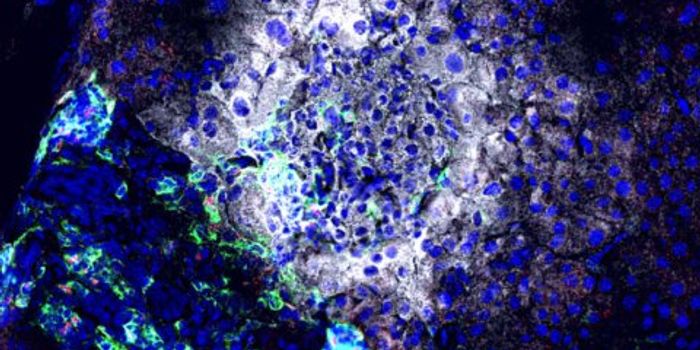

MAR 17, 2015CancerVanderbilt University researchers have achieved the first "image fusion" of mass spectrometry and microscopy - a technic ...